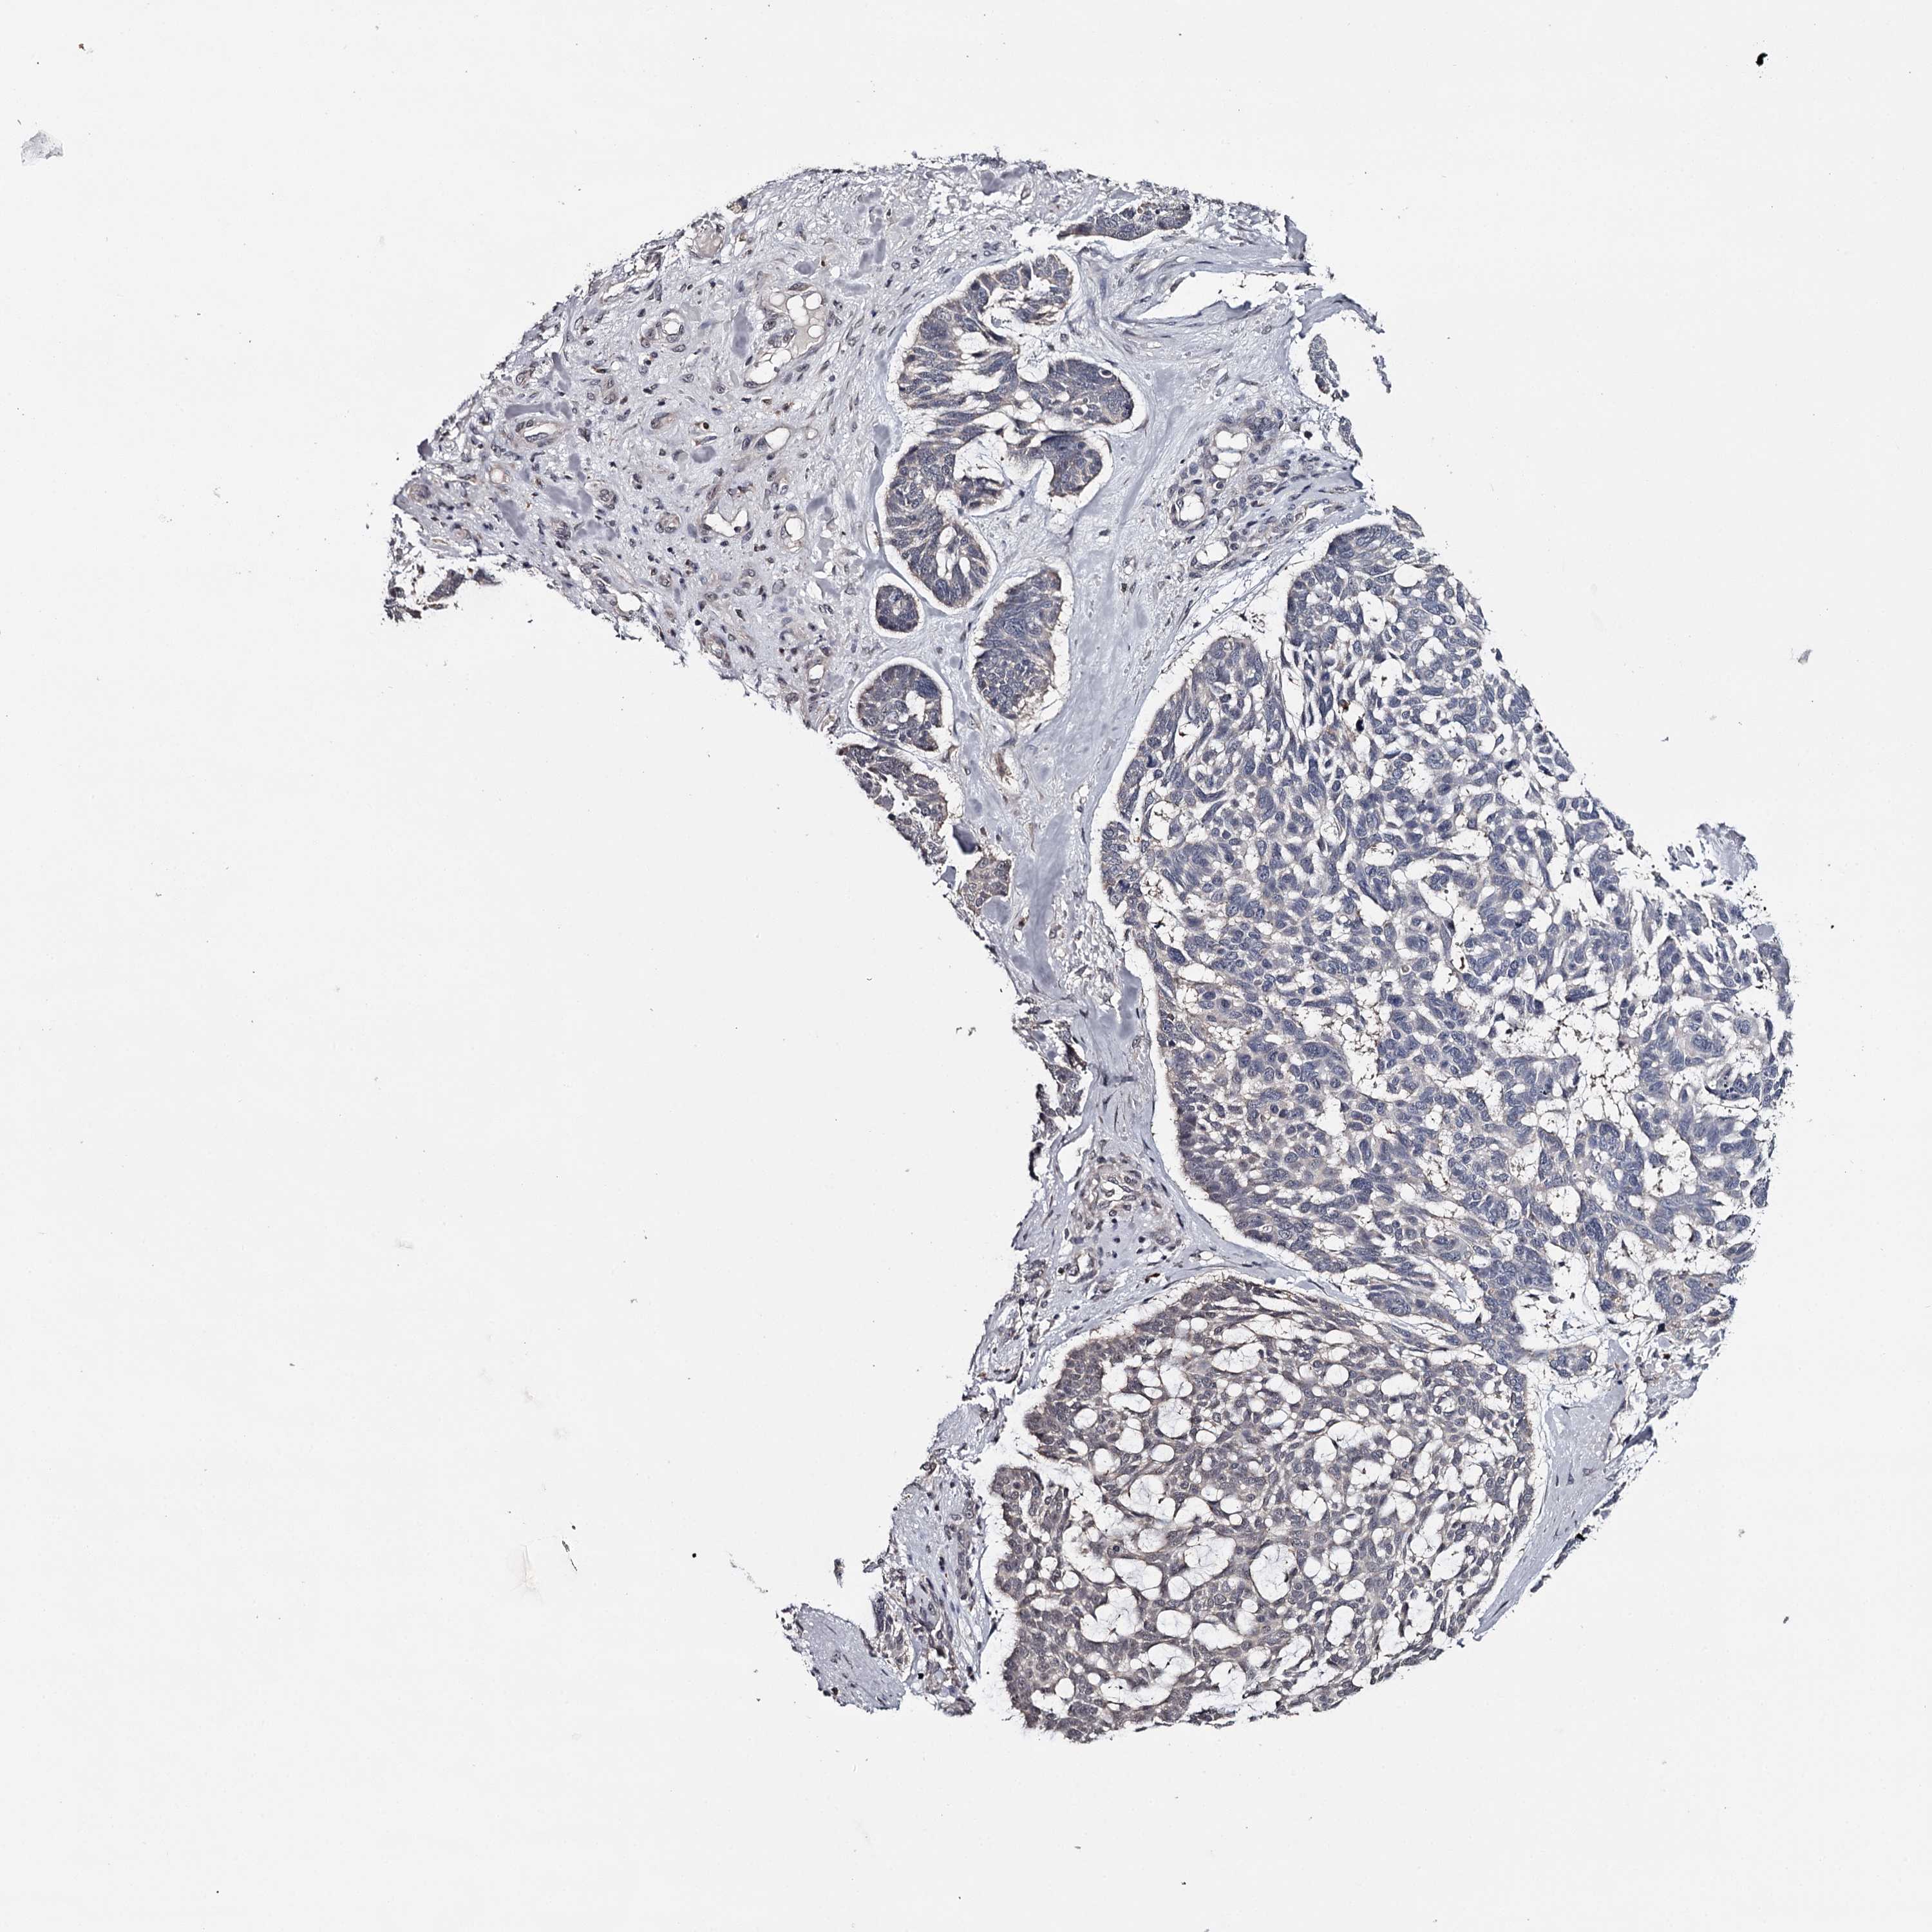

CANCER SKIN CANCER Show tissue menu

Basal cell and squamous cell cancer

SKIN CANCER - Protein expressioni

A mouse-over function shows sample information and annotation data. Click on an image to view it in a full screen mode. Samples can be filtered based on level of antibody staining by selecting one or several of the following categories: high, medium, low and not detected. The assay and annotation is described here.

Each image is clickable and will lead to virtual microscopy that enables deeper exploration of all samples and also displays staining intensity scores, fraction scores and subcellular localization as well as patient and tissue information for each sample.

Antibody HPA038876

Basal cell carcinoma

Squamous cell carcinoma, NOS

Squamous cell carcinoma, metastatic, NOS